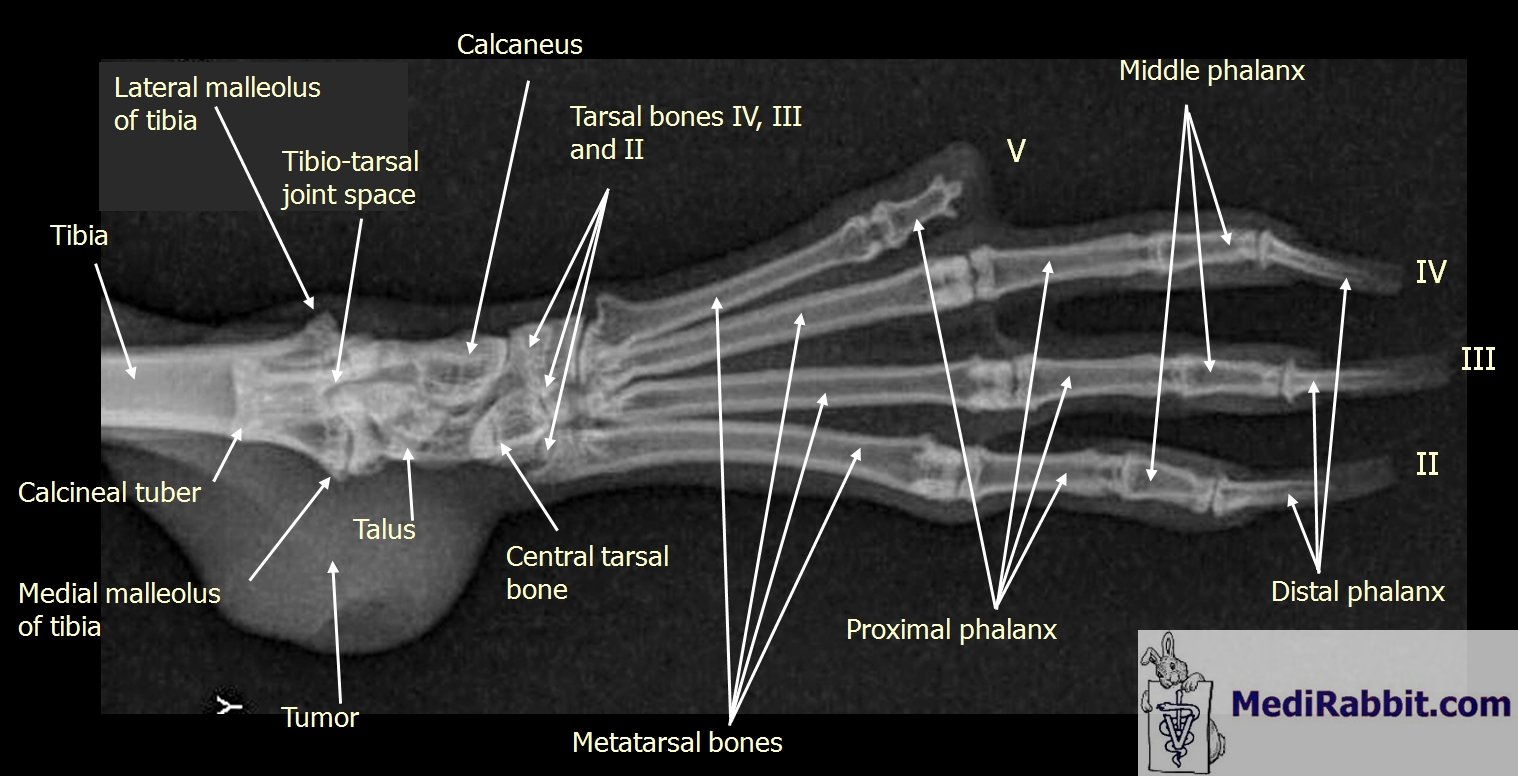

Ventro-dorsal radiography of the left hind foot

with a broken toe

The x-ray was taken after my rabbit Tilda hurt her toe. I had her in a transport box and was

lifting her up to her cage ("two-floor cage"). The door wasn't

closed properly and she jumped out before she could hop into her cage. She

fell on a hay holder attached to the cage and one of her legs was hurt before

she fell to the ground. We took her to the vet and as you can see the outer

toe on her left foot was broken. I closest toe was a little hurt as

well. The vet wanted to amputate but it was summer and both I and the

vet hesitated to do that. She pinned it and we went home. Unfortunately, my

rabbit kicked it off pretty quickly. She also got some antibiotics in case it

would be inflamed. It healed very well, however - one can't see that it has

been broken today, it doesn't point outwards as I've seen on other rabbits,

and she did her usual leaps of joys and running in the garden shortly after

(of course I limited her space first so she wouldn't run around with that

toe). We didn't do another x-ray after that. The only thing I’ve noticed is that the claw on

that toe doesn’t grow as well as the other claws. X-ray of broken toe